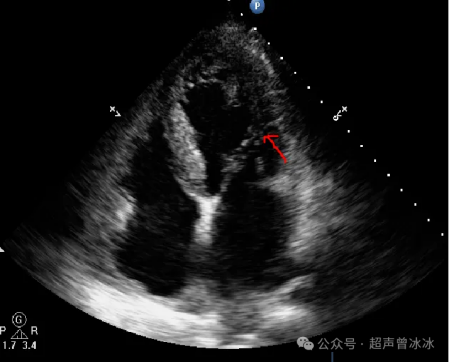

简单说来就是老吾老以及人之老,幼吾幼以及人之幼。前外侧乳头肌发出的腱索不仅管前叶,还管后叶,还管它们的交界区。同理后内侧乳头肌。反过来说,二尖瓣前叶和后叶发出的腱索是可以连到同一个乳头肌上的。

837b4fb97a65500fa426a200975b022e6d31eeff

千万不要误认为是降落伞样二尖瓣(只有一个乳头肌,前后叶的腱索都连在这一个乳头肌上)

怎么鉴别?

打个乳头肌短轴切面看看就知道啦-----一组乳头肌就是降落伞,两组就是正常的。